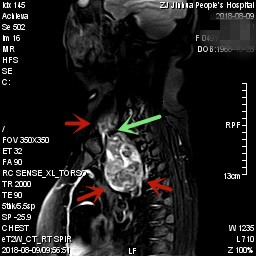

上图均示MRI下的肿瘤情况,红色箭头示肿块

上图示颈部与胸内的病灶关系密切,但绿色箭头处似有分界,仅少许相连